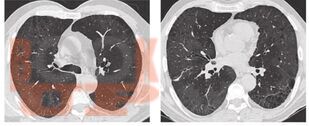

В настоящем учебном пособии освещены принципы ведения пациентов диссеминированными заболеваниями легких. Обсуждаются вопросы этиологии, патогенеза, диагностики, а также основные методы лечения пациентов с фиброзирующими альвеолитами. Учебное пособие предназначено для врачей общей практики, участковых терапевтов, аллергологов, пульмонологов.